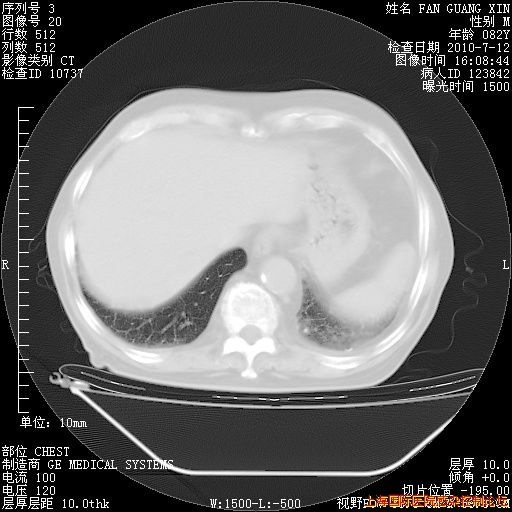

补发6月12日肺部CT肺窗

6月12日肺窗

今天复查CT

今天CT

整整相隔30天的肺部CT好像有所好转啊。甲强龙减量第3天,需要观察体温。

海管,自昨日你和我通完话后,不知您岳父消化道症状有无缓解?体温怎样?阅读7.12日胸部ct,个人认为目前激素治疗是有效的,甲强龙减量是适宜的。因在抗痨治疗,需密切观察肝功、肾功能和血常规。不过,老年、长期住院和大量使用激素,很担心菌群失调发生